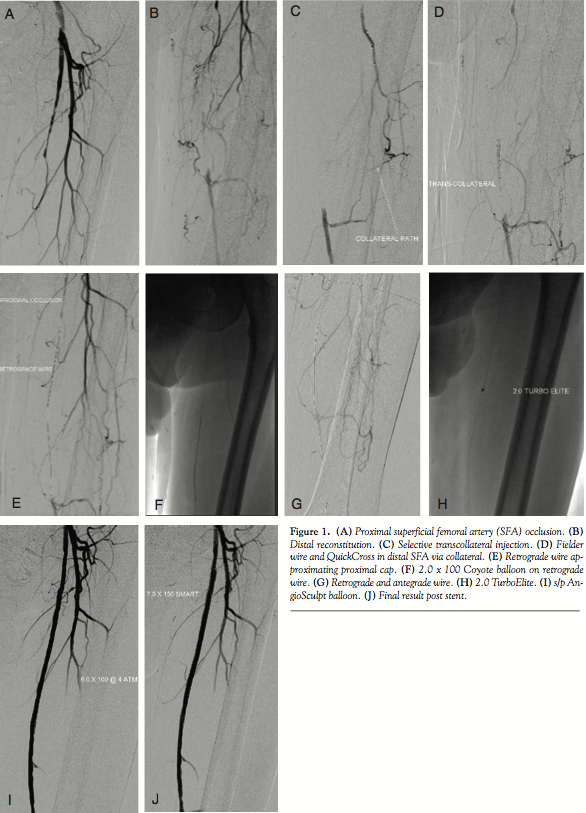

Case Report. A 65-year-old male presented with a history of atrial fibrillation, non-ischemic cardiomyopathy, tobacco abuse, hypertension and hypercholesterolemia. He had been complaining of progressive claudication. He was started on a trial of medical therapy including smoking cessation, cilostazol, and a walking program. The patient continued to smoke and despite medical therapy complained of lifestyle-limiting claudication. He underwent diagnostic angiography and was found to have high-grade stenosis of the right SFA and complete occlusion of the left SFA (Figures 1A and 1B) and two-vessel run-off with an occluded anterior tibial artery. He was referred for percutaneous revascularization of the left SFA.

The right common femoral artery was accessed using a 4 Fr micropuncture kit (Cook Medical).The sheath was upsized to a 5 Fr Avanti sheath (Cordis Corporation); using a 5 Fr IMA catheter (Boston Scientific) and an exchange-length glidewire (Terumo Corporation), the catheter was advanced into the left common femoral. The sheath was then upsized to a 6 Fr, 45 cm Pinnacle destination sheath (Terumo Corporation) placed in the origin of the left SFA. After administration of heparin, an Asahi Miracle Bros 6 wire (Abbott) was advanced to the cap. A Wildcat catheter (Avinger) was then advanced over the wire distally. An attempt to engage the cap resulted in deflection of the Wildcat into the collateral. Several attempts were made using the back end of the wire advanced to the distal tip of the catheter to provide more support while utilizing the Wildcat in different modes. Repeated attempts resulted in advancement of the device into the collateral branch. Next, an angled 0.18˝ QuickCross Extreme (Spectranetics) was used with a Treasure 12 guidewire (Abbott). Multiple attempts were made to advance the Treasure 12 wire into the proximal cap. It was felt this might allow advancement of the Wildcat to the cap without concern of deflecting into the collateral. Unfortunately, the proximal cap could not be penetrated secondary to the calcium as well as the angle and presence of a collateral. At this point, consideration was given to using an angled glidewire and QuickCross catheter and attempt a subintimal approach or bring the patient back for popliteal access. After further examination of the angiograms and angulated views (ipsilateral 20°), it was felt that there was an adequate collateral to attempt transcollateral passage of a wire. The destination sheath was withdrawn into the left common femoral and the wire was advanced into the collateral utilizing a Runthrough wire (Terumo Corporation) and a Finecross catheter (Terumo). Due to poor visualization of the catheter, the Finecross was exchanged for a 0.14˝ QuickCross and the wire was exchanged for a 300 cm Asahi Fielder wire (Abbott). Selective injection was then performed of the collateral through the QuickCross (Figure 1C). The Fielder wire was negotiated through the collateral and into the distal lumen of the SFA (Figure 1D). The 0.14˝ QuickCross was then advanced into the SFA in a retrograde manner and the wire was changed to an Asahi Confienza wire (Abbott). The wire was advanced in a retrograde manner through the calcified lesion to the proximal cap (Figure 1E). The cap could not be penetrated despite attempts with several wires (Confienza, Cross-It, Pilot 300). At this time, the 0.14˝ QuickCross was exchanged for an 0.18˝ QuickCross through the collateral in a retrograde manner. The wire was then changed to a Treasure 12 wire, which easily penetrated the cap. The wire was then advanced into the left common femoral artery and exchanged for a Runthrough wire. Several attempts were made to rewire the sheath or rewire an angled catheter. This was in order to externalize the wire and proceed with revascularization. These attempts were unsuccessful. Multiple attempts were made to snare the wire by utilizing a 2.0 mm loop snare (eV3). This also was unsuccessful. At this point a 2.0 x 100 Coyote balloon (Boston Scientific) was advanced via the collateral into the lesion in a retrograde manner. The vessel was dilated at 6 atm for 20 seconds (Figure 1F). At this point, a Fielder wire was easily advanced in an antegrade manner into the tibioperoneal vessel and then exchanged for a RunThrough wire (Figure 1G). A 2.0 TurboElite Laser fiber (Spectranetics ) was then utilized to debulk and modify the plaque as well as facilitate balloon delivery (Figure 1H). The lesion was predilated with a 6.0 x 100 AngioSculpt scoring balloon at 4 atm x 2 minutes (Figure 1I). This was performed in an overlapping manner. This was then followed by placement of a 7.0 x 150 SMART stent (Cordis), which was postdilated with a 7.0 x 100 Sterling balloon (Boston Scientific) at 4 atm (Figure 1J). Final angiography demonstrated brisk flow without embolization, perforation, or dissection. The sheath was withdrawn and a Mynk closure (AccessClosure) was performed of the right groin. The patient was discharged home the following morning without incident.